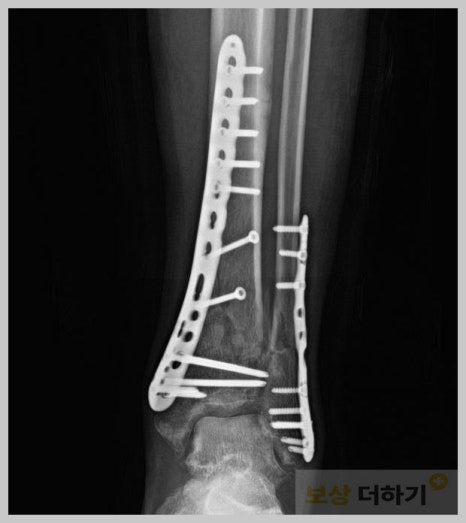

사례 2. 발목 골절

정 ** 님은 마주 오던 차와 충돌하는 교통사고로 발목 골절이 되는 부상을 입으셨어요. · 경골 및 비골 원위 분쇄골절 · 내외부 핀, 금속 고정 수술 아래쪽 다리뼈를 구성하는 경골과 비골의 하단이 모두 손상되었고, 뼈가 여러 조각으로 부서진 복잡한 형태의 손상이었기 때문에 보존적인 방법으로는 치유를 기대할 수 없어 수술이 시행되었습니다. 객관적인 장해 진단 및 합의 정 ** 님은 가해자가 있는 교통사고였고, 이때는 맥브라이드 방식으로 장애 진단을 해야 하죠. 해당 사고로 인해 얼마큼의 노동 능력이 상실되었는지가 핵심인데요. 이러한 부분들을 의사분들이 모두 알고 기재해 주시기는 어렵습니다. 치료에 대해 전문가이지 보상과 배상에 대해서는 아니기 때문입니다. 5,500만 원 지급 「보상 더하기」 손해사정사는 객관적인 장애 평가와 손해액 산정을 통해 적정한 합의금이 지급되도록 도움드렸는데요. 족관절의 강직 및 신경 손상으로 적정한 장해율을 인정받아 위자료, 일실수입 등에 적용하여 최종 5천5백만 원이 넘는 합의금을 받으셨습니다.